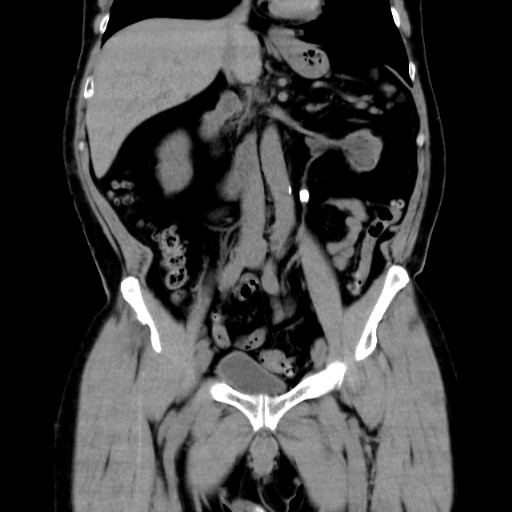

直腸肛門疾患に特化したCT撮影法

当院では、肛門・直腸疾患に特化した独自のCT撮影法を行っています。

従来の腹部CTが仰向けで撮影するのに対し、この方法ではうつぶせで撮影し、さらに直腸の形や走行に合わせて断面角度を調整することで、肛門周囲の病変をより鮮明に映し出すことが可能です。

また、3D画像によって痔瘻の走行を立体的に描出することもできます。

一般的撮影法

肛門病変に特化した撮影法